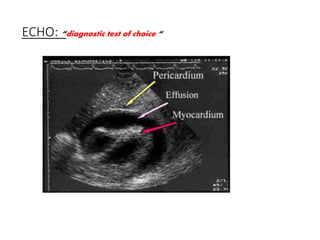

ECHO: “diagnostic test of choice “